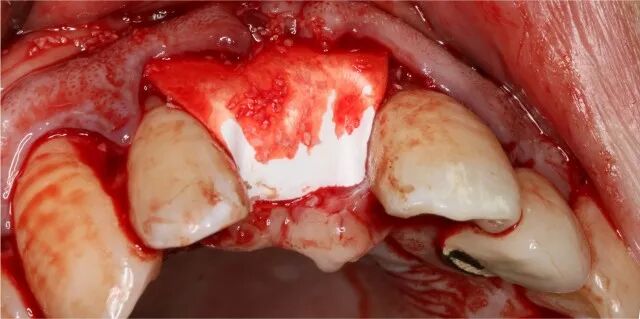

2.骨修復(fù)型手術(shù)實例二

骨修復(fù)型手術(shù)實例二

拔牙4個月后

植骨

覆蓋吉特瑞

種植及成骨效果